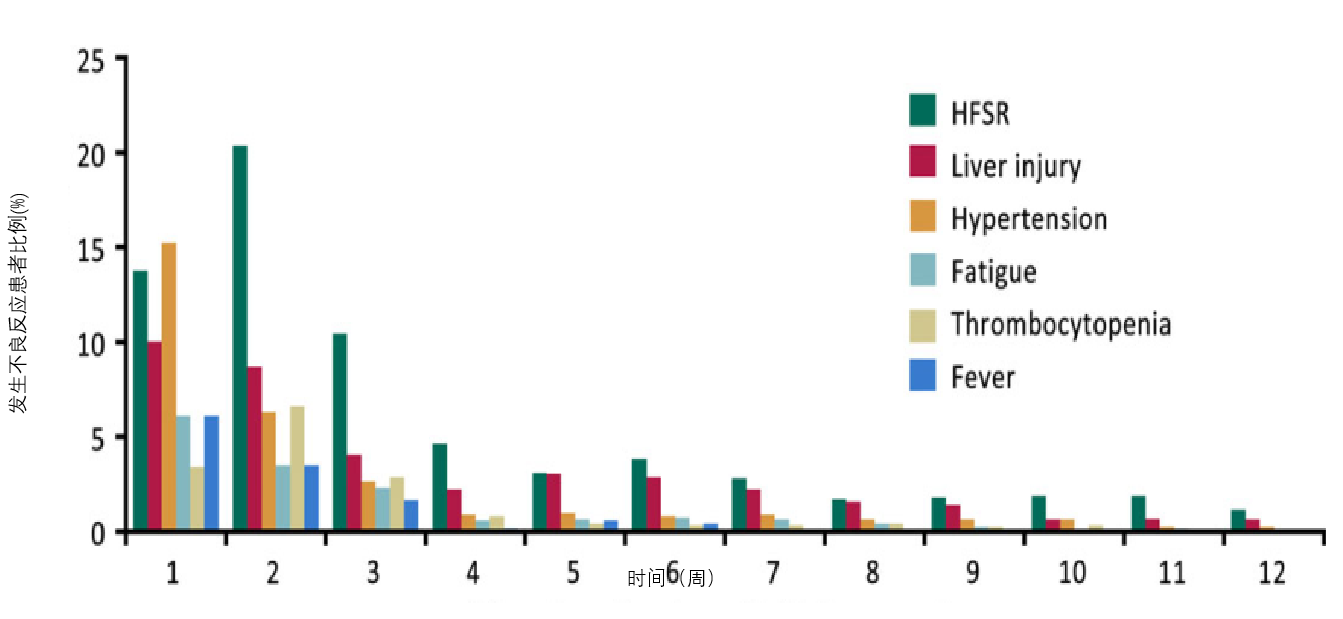

日本PMS真实世界研究

不良事件一般在治疗早期发生,且发生率随时间呈下降趋势